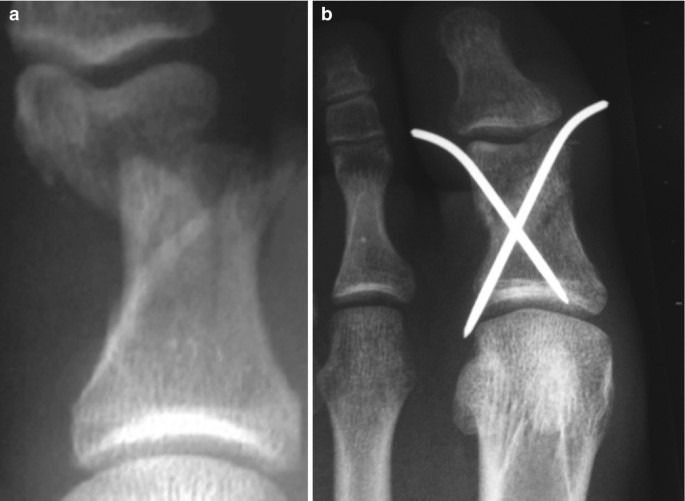

- 정복: 뼈의 위치가 어긋난 경우, 국소마취 하에 제자리로 맞춤

- 고정: 부목, 깁스, 테이핑으로 3~6주간 고정

- 수술: 금속 핀, 나사, 철심을 이용한 내고정술 시행(개방성·분쇄성 골절 등)